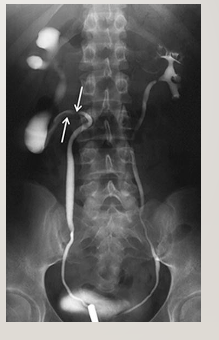

Structursal abnormalities in ureters

What is a retrocaecal/circumcaval ureter

Ureteric stones